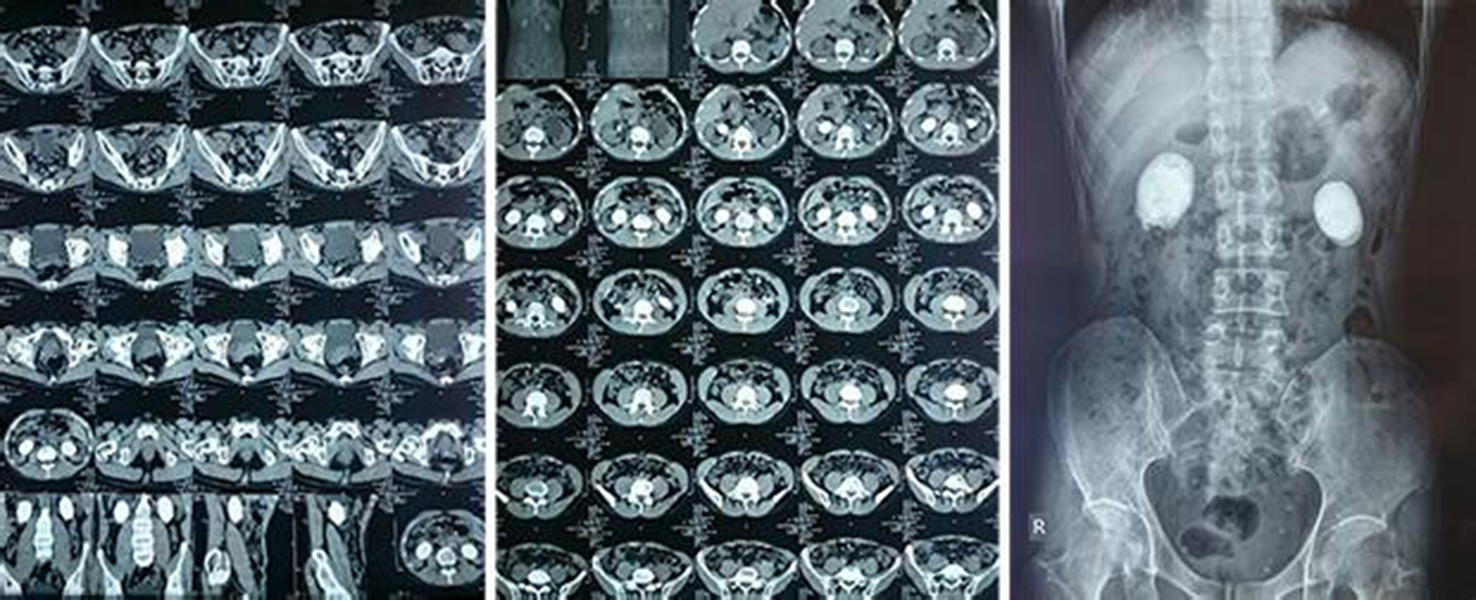

腎結石CT2

腎結石CT3